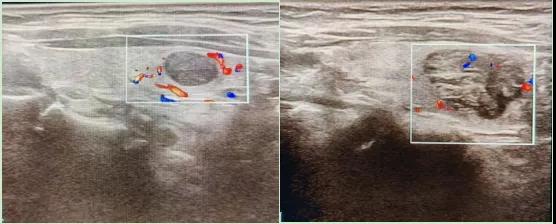

二、彩超如何“揪出”甲狀腺瘤?

彩超是一種無創(chuàng)、無輻射的檢查手段,被譽(yù)為甲狀腺的“高清攝像頭”。它的原理是:

超聲波探測(cè):通過發(fā)射高頻聲波,生成甲狀腺的實(shí)時(shí)圖像。

彩色血流顯示:用紅藍(lán)色標(biāo)記血流信號(hào),區(qū)分腫瘤的供血情況。

醫(yī)生會(huì)通過以下特征判斷腫瘤性質(zhì):

1.形態(tài):良性多呈圓形,邊界清晰;惡性可能不規(guī)則、邊緣模糊。

2.回聲:低回聲結(jié)節(jié)風(fēng)險(xiǎn)較高(像“烏云”一樣暗)。

3.鈣化:細(xì)小砂礫樣鈣化提示惡性可能。

4.血流信號(hào):惡性結(jié)節(jié)常有豐富紊亂的血流。